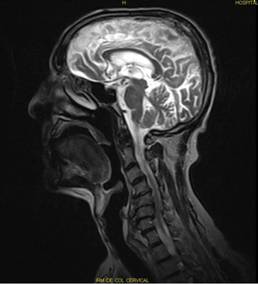

Resonancia magnética nuclear de cráneo y de columna cervical, secuencias sagital, transversal y mielocoronal: Se observaron cambios en la intensidad de señales a nivel de la sustancia blanca periventricular y en centros semiovales, sugestivo de isquemia en esos territorios, además de aumento de los espacios subaracnoideos corticales, compatible con atrofia cortical, con dilatación ventricular compensatoria y cambios osteodegenerativos con formación de osteofitos marginales cervicales anteriores y posteriores, estrechamiento de los espacios intervertebrales y deshidratación de los discos. Por otra parte, se visualizaron complejos disco-osteofitos en las vértebras C3, C4 y C5, que comprimían la columna de líquido, y en C5, C6 y C7, que provocaban supresión de esta. En secuencia de mielo existía borramiento total derecho e izquierdo, además de imagen hipointensa en cuerpos vertebrales C6 y C7, compatible con edema óseo y compresión anterior del saco dural, con estenosis del canal (Fig.1.).